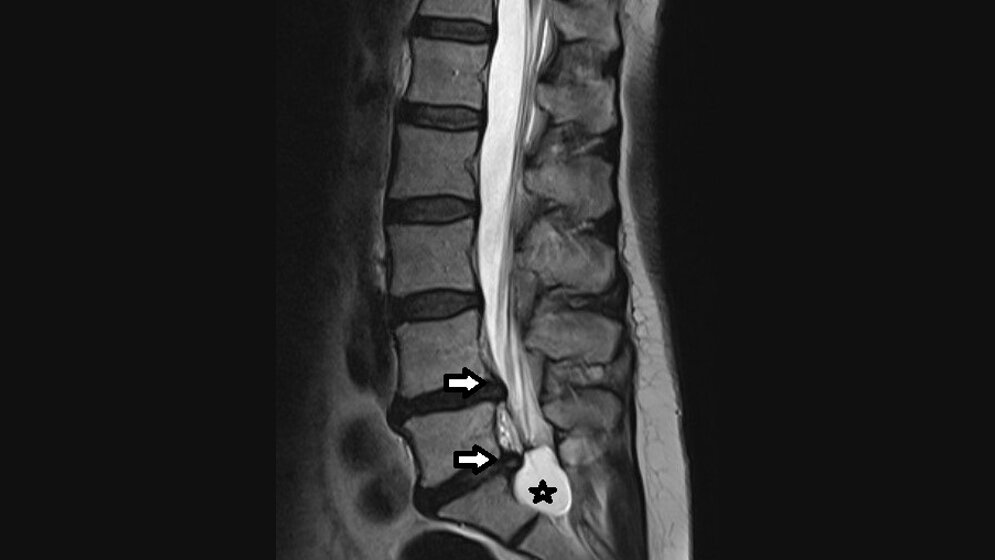

Asymptomatische Zysten der Wirbelsäule, insbesondere der sakralen Nervenwurzel, haben eine Prävalenz von 5 %. Die Magnetresonanztomografie ist die beste Methode, sie nachzuweisen. Die Zysten können sakrale oder perineale Schmerzen verursachen, radikuläre sensomotorische Symptome sowie neurogene Blasen- und Mastdarmstörungen, abhängig von ihrer Größe und Lokalisation.

Asymptomatic cysts of the spine, especially of sacral nerve roots have a prevalence of 5 %. MRI is the best method to demonstrate it. The cysts may cause sacral or perineal pain, radicular sensomotory symptoms and neurogenic bladder and bowel dysfunction depending on their size and location.